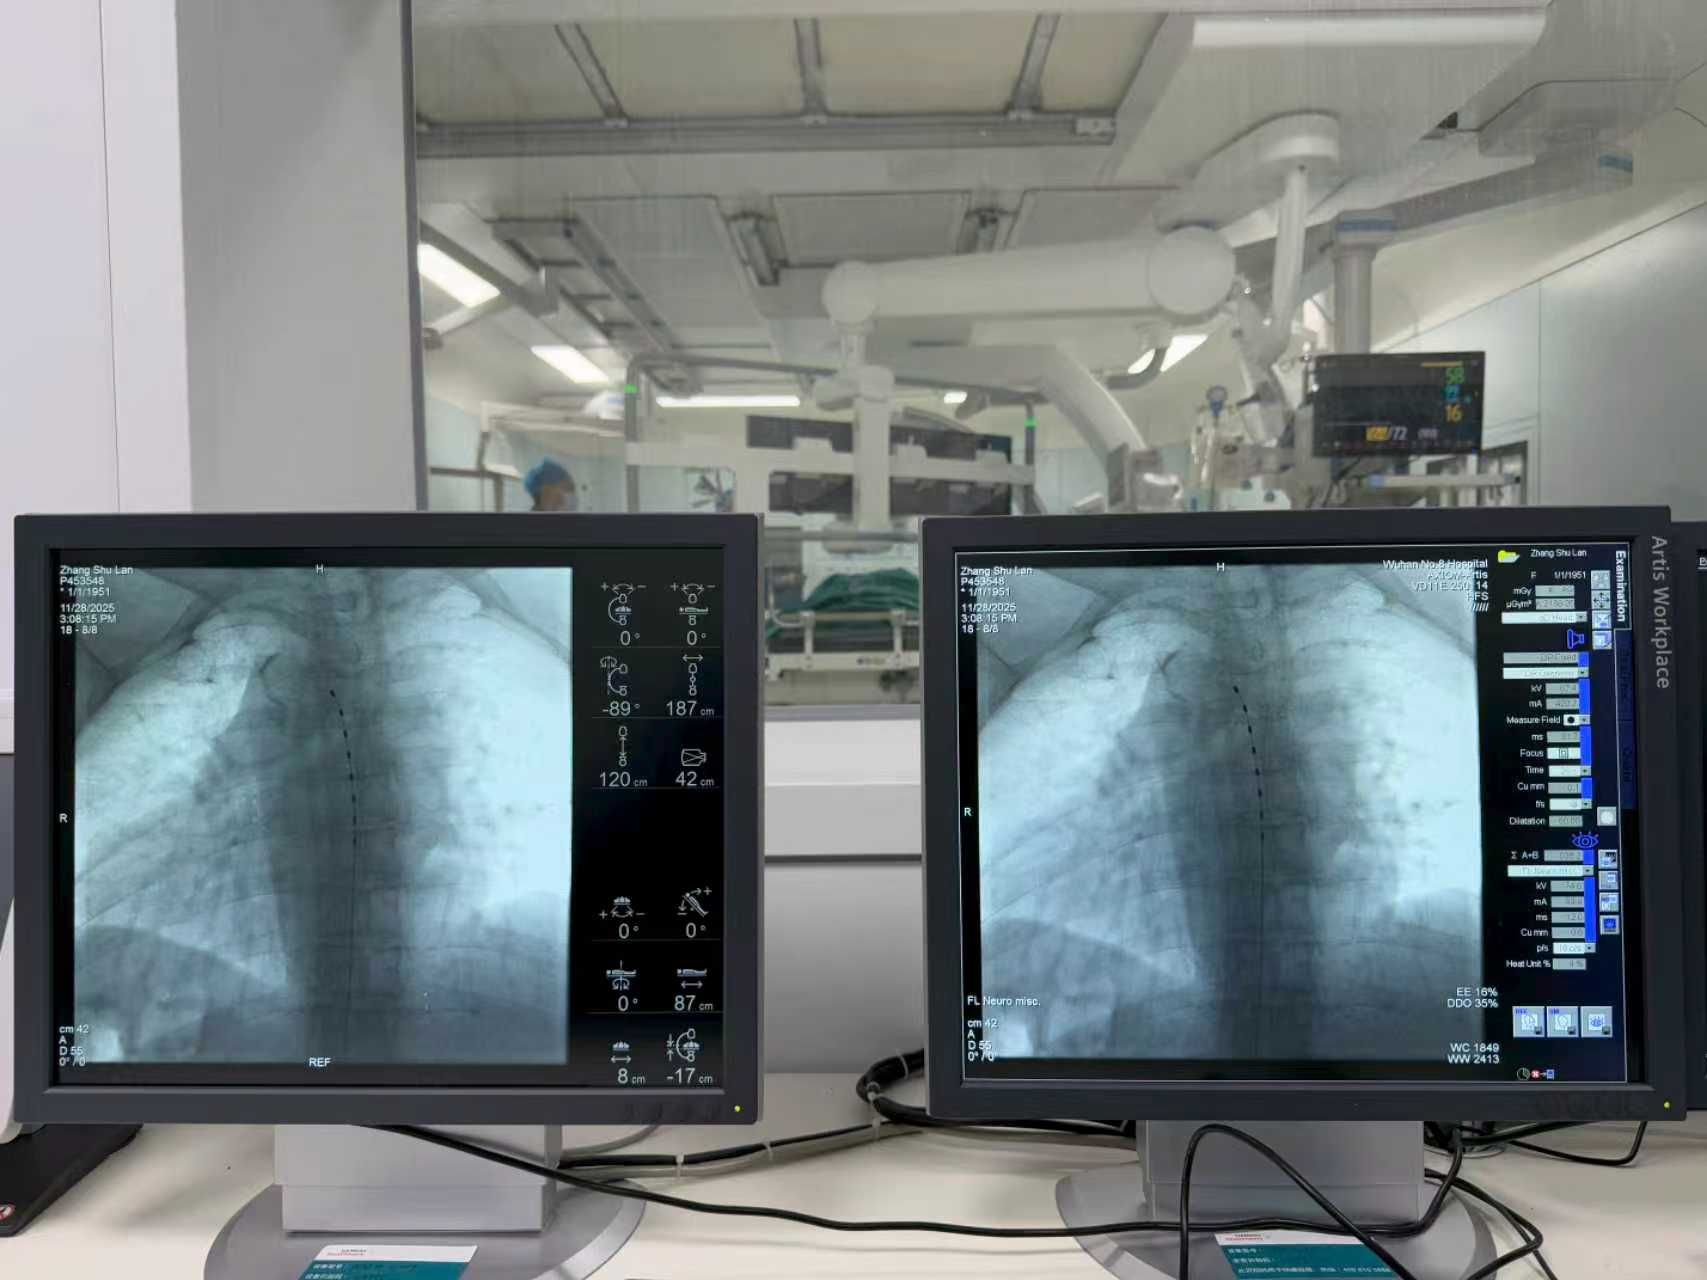

考虑到张阿姨脊柱存在旋转侧弯,电极植入难度较高,吴群主任团队凭借丰富的临床经验,在数字减影血管造影机全程引导下,成功将刺激电极精准植入预定脊髓节段。术中开机测试时,张阿姨立即感受到原先剧烈疼痛的区域被舒适的麻刺感覆盖,疼痛显著减轻。术后,张阿姨情况稳定,在医护人员指导下早期即可开展床旁活动,恢复顺利。

通过DSA的引导,医生精准将电极植入到硬膜后外间隙之间。